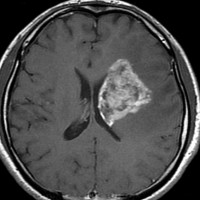

アバスチン投与後15日目

たった2週間で劇的な改善が見られました。失語症と片麻痺や認知機能も改善しました。

4回目のアバスチン投与後

アバスチンをどれだけ続ければいいのかははっきりしていません。2週間おきに6コースまでの投与が基本かもしれません。

この画像を見ると,放射線とテモダールの治療が有効であったのかなと思います。